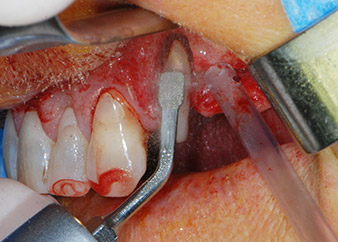

However, we maintained our initial plan to retain both teeth as temporary bridge abutments during the six-months osseointegration period of the implants. At reentry, the situation would have to be reassessed. First, in an attempt to manage the endo-perio problem, the remaining root surface was carefully debrided with piezoelectric equipment (Piezomed, W&H, used with the spatula-shaped insert S1, originally designed for erosion of the lateral sinus wall) (Fig. 4).

periodontium

Fig. 4: To preserve the tooth as a temporary abutment, the periodontium was debrided with piezoelectric equipment …

buccal apex of tooth 24

Fig 5: ... and the buccal apex of tooth 24 was abraded with the same instrument (apicoectomy).